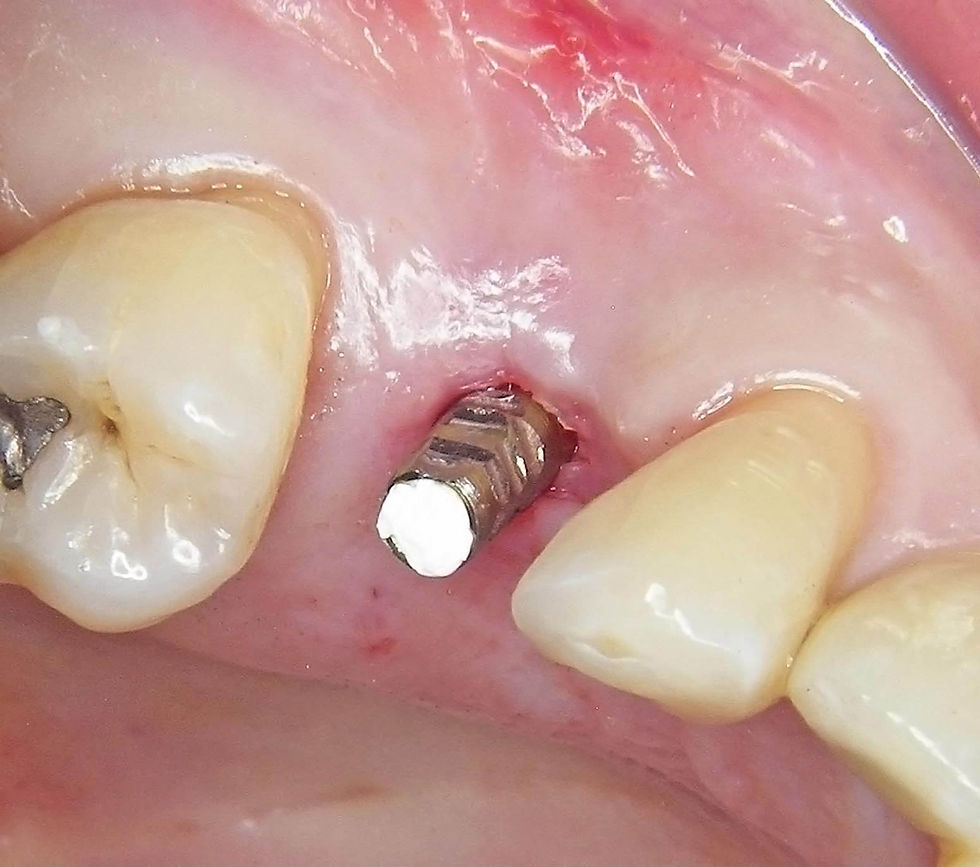

Positioning of a post with retentive notches and occlusal perforation of the old metal-ceramic crown to access to the prosthetic screw.

The crown is filled with self-curing resin with the application of a thin layer of cyanoacrylate to improve its adhesion to the inner metal of the crown. Then the crown is placed on the post with the access to the screw protected by compacted Teflon.